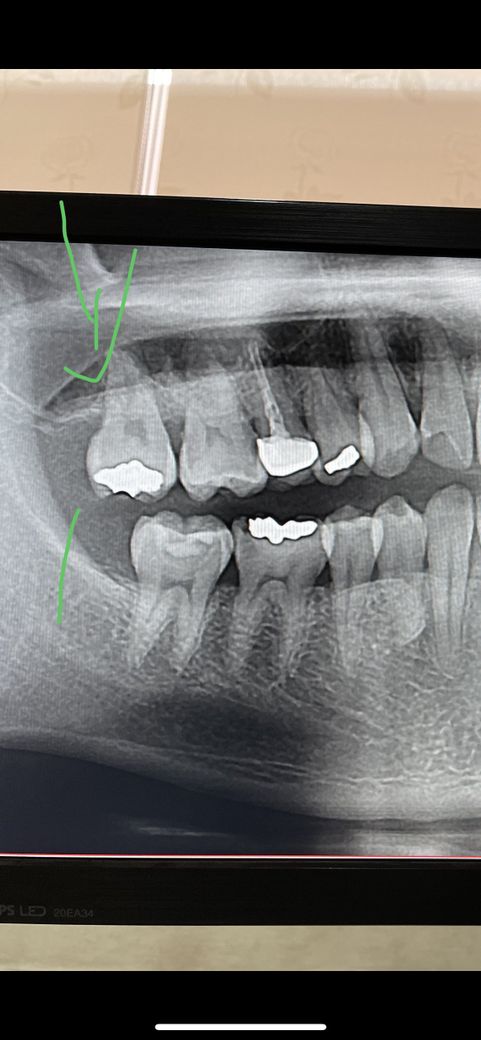

사진으로 봣을대 잇몸이 안조은가요?…음식물이 유독 잘끼긴 합니다…

물론 사진으로 보았을 때도 앞 치아에 비해 잇몸라인이 내려갔습니다. 하지만 잇몸이 내려간다고 해서 지금의 증상이 나타나는 것은 아닙니다. 아마 치아 자체의 문제가 더 커 보입니다.

사진으로만 봤을때는 특별히 이상이 없어보입니다.

씹을때 불편감을 느끼긴다면 치아에 금이갓을 경우에 그럴수도 있습니다. 치아에 금이갓다면 신경치료를 하셔야될수도 있습니다. 잇몸뼈가 많이 내려가셧고 잇몸이 좋지는 않아보입니다